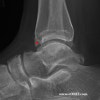

X-ray에서 경골 전방 가장자리, 거골 활차부 전방 가장자리에 외골종 양상의 골 증식 변화가 나타날 수 있습니다.

X-ray : 발목 충돌증후군(Anterior impingement)